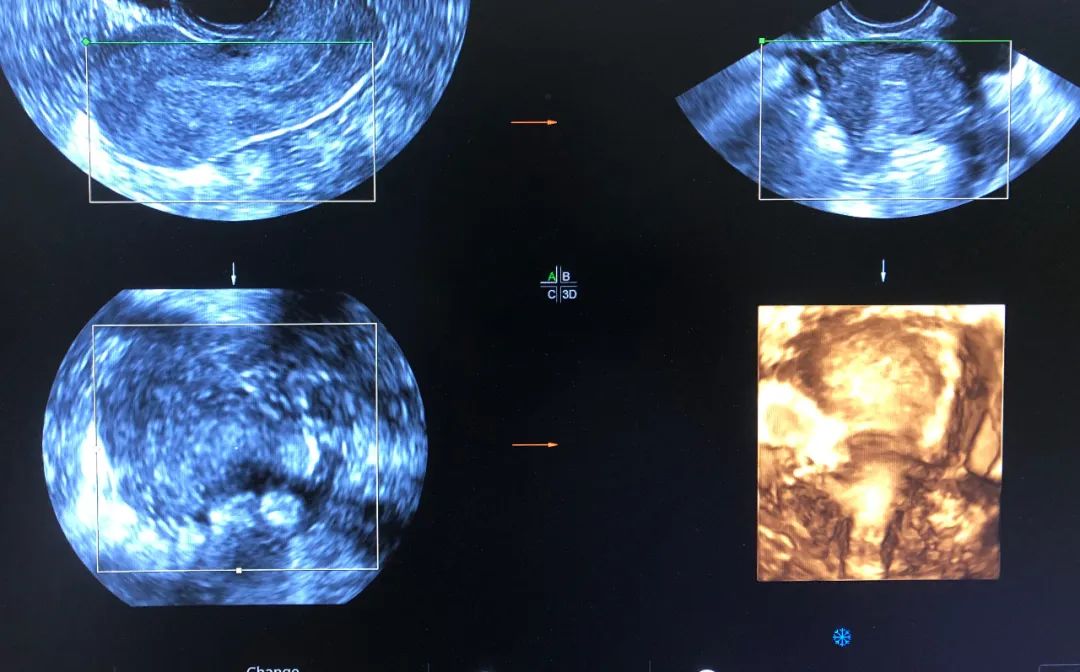

超声诊断弓形子宫 (大荔县妇幼保健院四维彩超)

6月2日,一患者因外院超声诊断不全纵隔子宫来市妇幼院就诊,经常规妇科超声检查并未发现明显纵隔,与患者沟通后行经阴道四维超声检查,得到了清晰的图像诊断为弓形子宫,为妇科临床诊断提供了可靠依据。

腔内四维超声(4D-TVS)是在腔内二维超声基础上,利用计算机处理发展起来的新型超声诊断技术,可以提供更多的诊断信息,具有常规经阴道超声无法比拟的优势,立体直观,功能强大,可实现360度全方位无死角成像,大大弥补了单纯二维腔内超声的不足。

腔内四维超声检查可对先天性子宫畸形(完全或不完全纵隔子宫、弓状子宫、双角子宫、单角子宫、残角子宫等)、宫腔粘连、内膜息肉、粘膜下肌瘤进行诊断及鉴别诊断,还能清晰的观察到节育器的形态、位置,大大提高了超声在妇科疾病诊断中的准确率,为临床医生提供更准确的诊断信息,同时填补了我市在此项技术的空白。